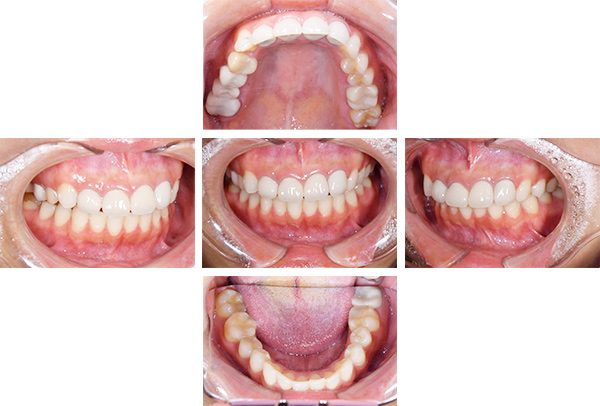

インレー・クラウン症例

治療前

治療後

治療期間 4回(3ヶ月)

費用 ・セラミックインレー11本

・ジルコニアクラウン1本

合計:660,000円

治療リスク・副作用 ・詰め物、被せ物をする時は自分の歯を削ることになります

・歯ぎしり・食いしばりが強い方は、セラミックが割れてしまうことがあります。